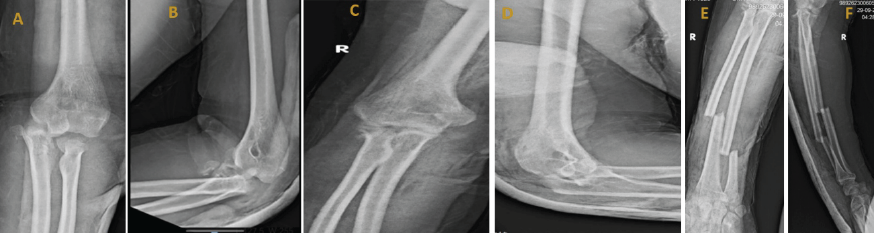

A right-hand dominant male in his late 20s, with a known history of schizophrenia on regular medication, presented to the emergency department of a tertiary care center after sustaining a fall from a height of 18 feet. On arrival, he was managed according to advanced trauma life support protocols. The primary survey was conducted immediately, confirming a patent airway with cervical spine protection, spontaneous breathing with symmetrical chest movement, and hemodynamic stability (C-spine cleared clinically and later radiologically). Circulation was assessed with bilateral feeble lower limb pulses, and intravenous access was established. There were no signs of active bleeding or tension pneumothorax. A focused neurological examination revealed that the patient was conscious and oriented, with no evidence of head injury or spinal cord involvement. Secondary survey revealed multiple orthopedic injuries and soft-tissue wounds over bilateral limbs, resulting in swelling and restricted ROM in both elbows, left knee, and both ankles, along with pain and tenderness over the lower back. Initial radiographic (Fig. 1) and clinical assessments revealed closed terrible triad injury of the right elbow and an open grade 1 terrible triad injury on the left elbow, i.e., bilateral dislocation of elbows, with radial head (right- Mason type III, left- Mason type IV) and coronoid process-associated fractures (Regan–Morrey type III- right, type II- left). Additional injuries included a right-side forearm fracture, comminuted open grade 2 distal femur and patella fracture on the left side, undisplaced fractures of the scaphoid, lunate, triquetrum, and distal radius on the left, open calcaneal and talar fractures on the right, closed pilon fracture, L1 vertebral body fracture (AO Type C), and multiple metatarsal and cuneiform fractures of the left foot. Three-dimensional (3D) computed tomography reconstruction of the elbows showed coronoid process fracture and comminuted radial head fracture on both sides (Fig. 2).

Figure 1: Pre-operative X-rays of left elbow (a) anteroposterior and (b) lateral view, right elbow (c) anteroposterior and (d) lateral view, right forearm (e) anteroposterior and (f) lateral view.